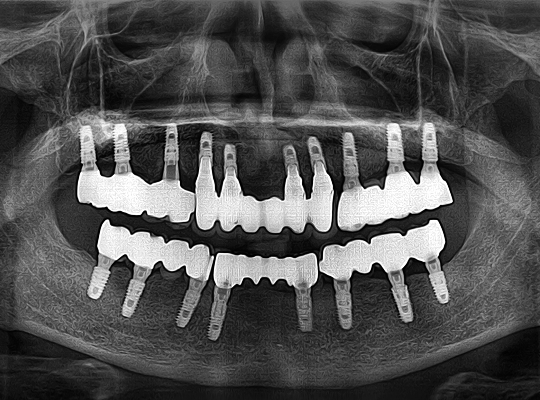

• 대한시니어치과학회 공식 인증 임플란트

• 고정력이 강하여 약한 잇몸뼈에도 잘 붙는다

• 임플란트 식립 후에 뼈 흡수가 적어 오래 사용 가능

• 강한 씹는 힘을 버티도록 설계

• 즉시 식립 및 즉시 식사에 특화된 임플란트

• 뼈이식을 안 하거나 거의 안 할 수 있다

• 추후 AS가 쉽다

• 자체 기술로 제작한 치아몸통을 연결하여

임플란트를 4~6개만 식립 가능

식립 개수를 줄이는

시니올 임플란트

시니올 임플란트의 보철물은

기존 방식으로는 제작이 어렵습니다.

젊어지는치과에서는 시니올 보철물 제작에

특화된 전담 의료진이 보철물을 직접 디자인하고,

당일에 제작하여 끼워드립니다.

수술 후 임시 틀니를 착용하지 않기 때문에

틀니로 인한 고통이 없을 뿐 아니라

수술 당일부터 식사가 가능합니다.